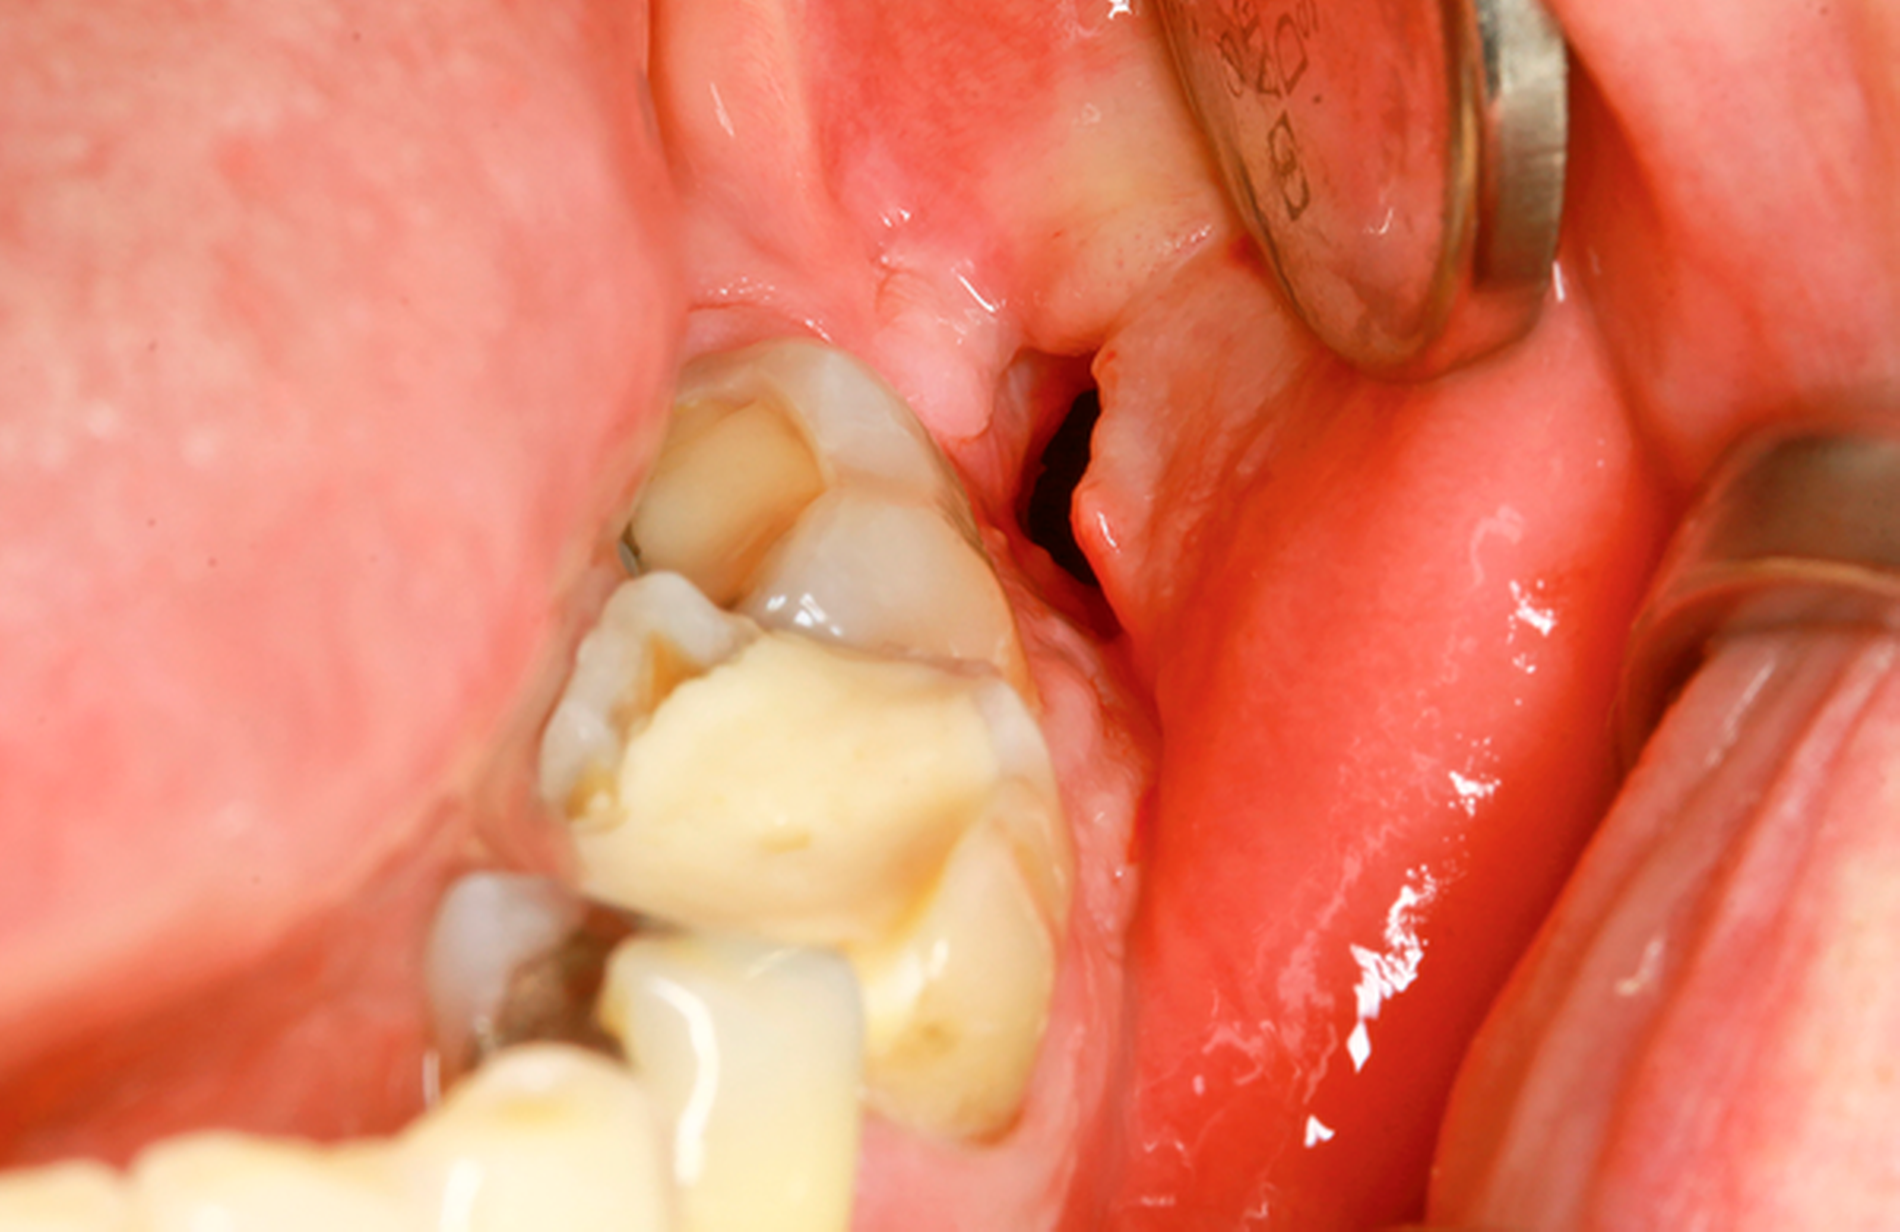

Eine 72-jährige Patientin wurde zur Therapie einer Zyste in regio 48 in unser MVZ überwiesen. Es handelte sich um einen Zufallsbefund im OPTG. Klinische Beschwerden wurden von der Patientin verneint (Abbildung 2a). Vorerkrankungen bestanden abgesehen von Migräne nicht. Zur Beurteilung der Zystenausdehnung erfolgte eine Computertomografie des Gesichtsschädels, die insbesondere eine basal stark ausgedünnte Kortikalis zeigte. Nach Erörterung der therapeutischen Möglichkeiten entschied sich die Patientin für eine Zystostomie, da die Zystektomie mit einem erheblichen Frakturrisiko, der möglichen Schädigung des N. alveolaris inferior sowie einer Behandlung in Allgemeinanästhesie verbunden gewesen wäre. In Lokalanästhesie wurde über einen marginalen Zugang in regio 47-48 eine Biopsie des Zystenbalgs gewonnen sowie eine Drainage ins Zystenlumen inseriert. Histologisch konnte eine follikuläre Zyste gesichert werden.